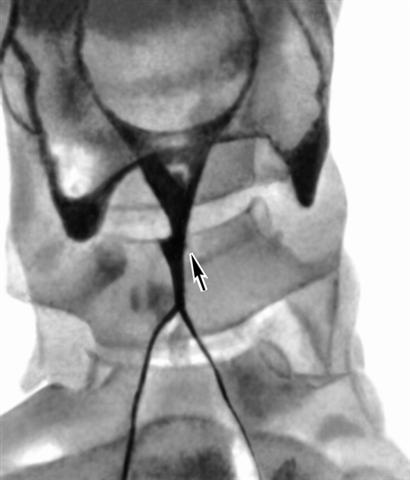

Рис. 2. Ларингограмма при раке гортани (прямая проекция): левый желудочек гортани не заполнен рентгеноконтрастным веществом (стрелкой указан дефект наполнения).